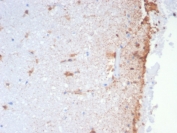

IHC staining of FFPE human brain tissue with GFAP antibody (clone GFAP/6881). Inset: PBS used in place of primary Ab (secondary Ab negative control). HIER: boil tissue sections in pH 9 10mM Tris with 1mM EDTA for 20 min and allow to cool before testing.